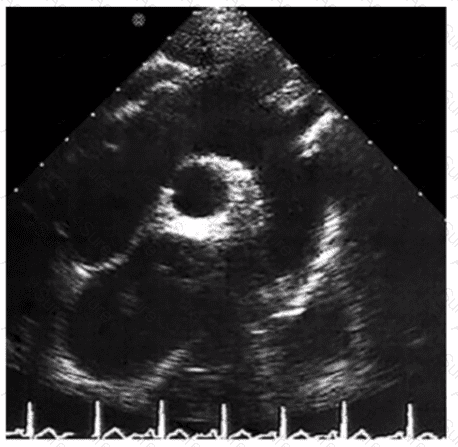

Identify the right pulmonary artery.